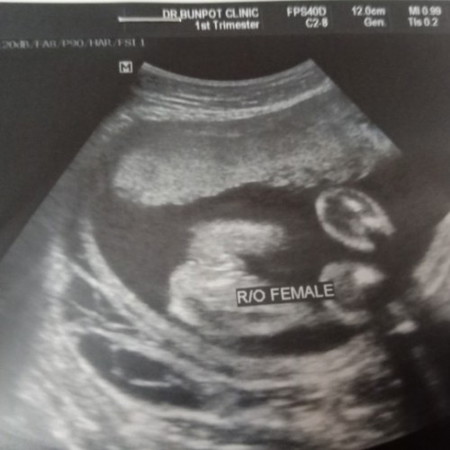

ภาพอัลตร้าซาวช่วยดูหน่อยจ้าว่าใข่เพศหญิงชัวๆเลยไหม 😀😀

ผู้หญิงจ้า